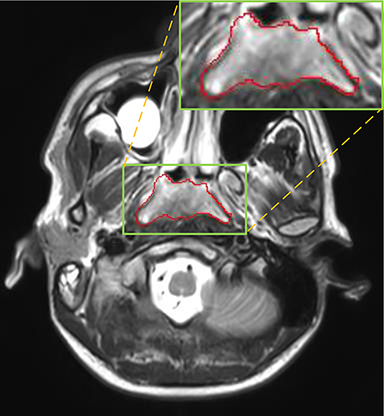

Currently, there is still no effort to fuse multi-modality MRI to develop an automatic segmentation system for NPC. According to researches of Popovtzer et al. [16], it should be a routine clinical practice to incorporate all kinds of MRI datasets in highly conformal radiation therapy to realize GTV delineation of NPC. For delineation of NPC, MRI is the perferred imaging modality for its superior soft tissue contrast [16, 3]. Moreover, MRI of different modalities data have different visual characteristics and various responses to different tissues and anatomical structures. For example, T1-weighted (T1) MRI is suitable for detecting skull base involvement and fat planes, while contrast-enhanced T1-weighted (CET1) MRI is used to identity tumor extent [3]. Figure 1 shows some examples of NPC response in T1, CET1 and T2-weighted (T2) MRI.

Comparison with ground truth. Some predicted results of MMFNet are shown in 2D images and 3D images in Figure 7 and Figure 8. As shown in these figures, although the shape and size of NPC are varied from each other, MMFNet can still accurately determine the regions of NPC and obtain the accurate contours of tumors. Through analyzing 2D images in figure 7, MMFNet has a capacity to fuse multi-modality MRI to reduce the confusion brought by intensity’ similarity between nearby tissues and NPC. The values of , and of MMFNet are shown in Table 1. MMFNet can reach the best results with , and .